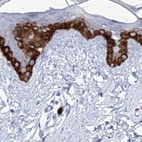

Immunohistochemical staining of human kidney, liver, lymph node and skin using Anti-FRS3 antibody HPA030174 (A) shows similar protein distribution across tissues to independent antibody HPA030162 (B).